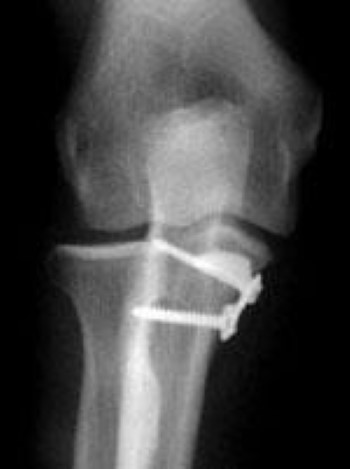

The elbow is made up of:

• The humerus (upper arm bone)

• The radius and ulna (the two bones in the forearm)

On the inner and outer sides of the elbow, strong ligaments (collateral ligaments) hold the elbow joint together and work to prevent dislocation/subluxation events. The two important ligaments are:

• The lateral (outside) collateral ligament

• The medial (inside) collateral ligament

The muscles that cross the elbow joint also contribute to the stability of the joint.

elbow anatomy

(Left) The bones of the elbow and forearm shown with the palm facing forward. (Right) The ligaments of the elbow.

Reproduced with permission from J Bernstein, ed: Musculoskeletal Medicine. Rosemont, IL, American Academy of Orthopaedic Surgeons, 2003.